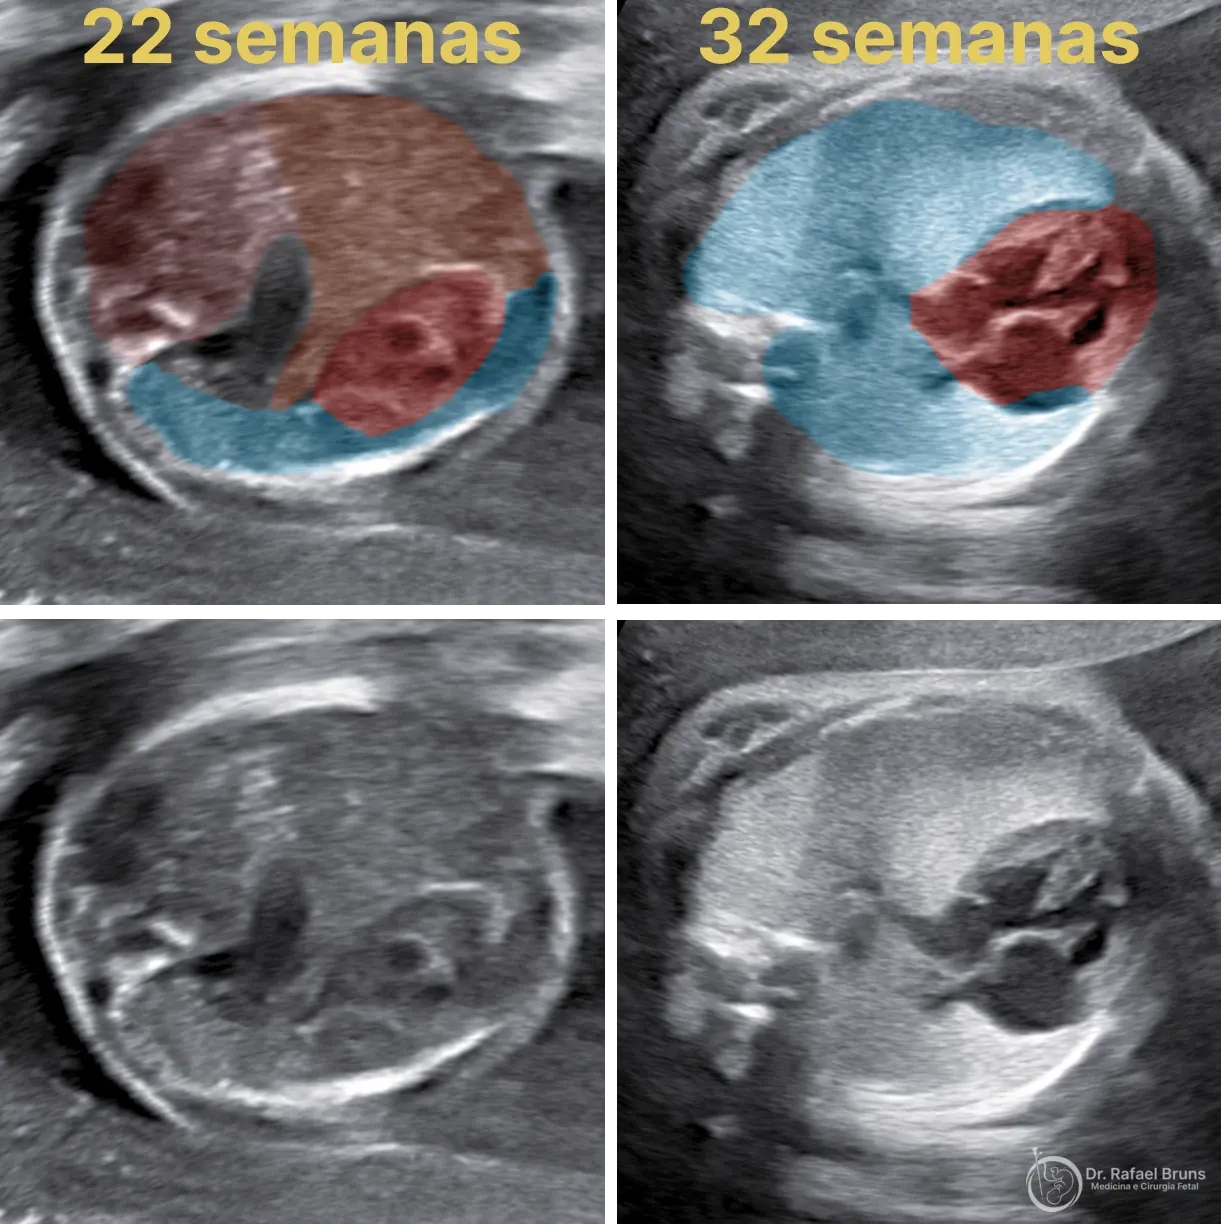

O diagnóstico é feito por ultrassom, geralmente entre 18 e 20 semanas de gestação, quando o exame morfológico identifica achados característicos: o coração desviado do seu eixo normal, vísceras abdominais visíveis no tórax, e pulmões menores do que o esperado para a idade gestacional.

Normalmente, os pulmões fetais produzem e secretam líquido pulmonar que flui para fora pelas vias aéreas. Com a traqueia ocluída pelo balão, esse líquido fica retido. O acúmulo progressivo gera uma pressão interna que força a expansão dos pulmões — mecanicamente, é um estímulo de distensão sustentada que o tecido pulmonar interpreta como sinal de crescimento.